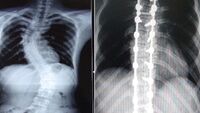

Ortopedi